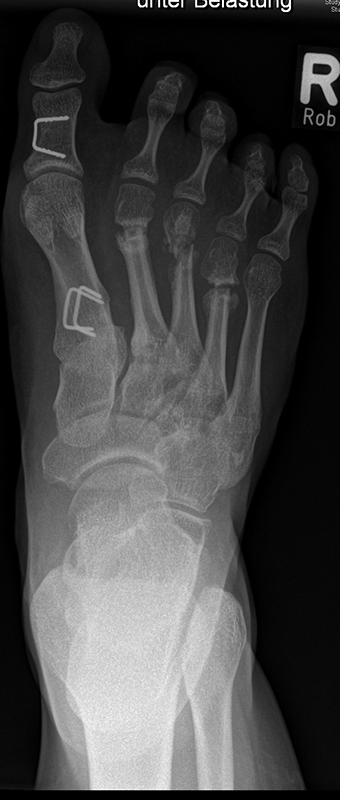

Knick-Senk-Platt-Fuß Korrektur mit dem Canalis Tarsi Spacer

In der Korrektur des schmerzhaften, aber flexiblen Knick-Senk-Fußes oder Plattfußes ist die Schraubenarthrorise mit einem Sinus tarsi oder besser bezeichnet als Canalis tarsi Spacer und alternativ mit einer Calcaneus-Stopp-Schraube seit vielen Jahren ein etabliertes Verfahren und führt zu einer kompletten Korrektur von flexiblen Knick- und Plattfuß-Fehlstellungen (Abb. 7). Die nötige Schnittlänge über dem Sinus tarsi beträgt für beide Verfahren 1 cm.

Abb. 7 a-e: Knick-Senk-Fuß prä- und postoperative Situation (a-b), ventrale und dorsale Ansicht (c-d). Laterale Ansicht des Hautschnittes über dem Sinus tarsi (e).

Zum Lesen der Bildbeschreibung und zur Vollansicht bitte die Bilder anklicken. Bilder: A. Helmers.